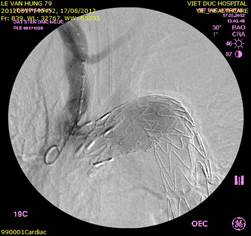

Ảnh: Hybrid trên quai ĐMC và tổn thương nhiều tầng của mạch máu:

Bắc cầu ĐM cảnh-cảnh P-T (BN 1) và đặt stentgraft quai ĐMC

Lóc tách type B vỡ vào khoang màng phổi T